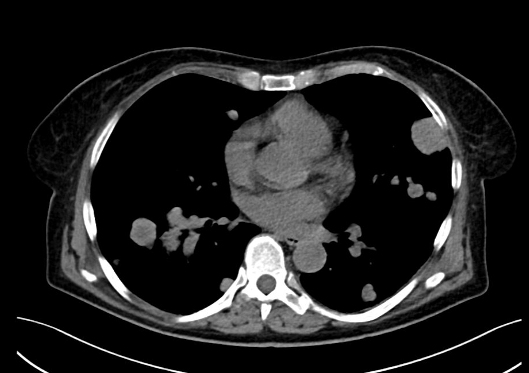

NO: 58letá žena, u níž byla na CT zjištěna objemná vaskularizovaná expanze pravé ledviny 10x12 cm bez trombózy, bez lymfadenopatie. Poté na CT zobrazeny četné plicní metastázy velikosti do 4 cm a metastáza na rozhraní acetabula a kosti kyčelní vpravo. Pod CT kontrolou provedena biopsie nádoru ledviny. Jedná se o tumor pravé ledviny (12 cm) cT2b cN0cM1 (plíce, pravá kyčel).

/ Obr. č. 1-5: CT hrudníku, břicha a pánve, patrná expanze pravé ledviny, plicní metastázy, lytická metastáza v pravé kyčelní kosti.